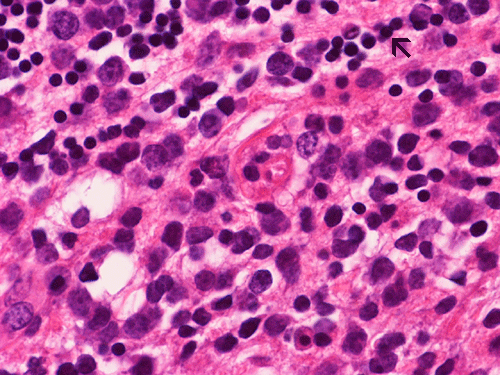

The biopsy material is obtained from the cerebellum. It is composed of two small fragments of semi-liquid dark, mucoid tissue, 0.4 x 0.4 x 0.2 cm in toto. Half is used for the cytologic preparation and the other half for frozen section. On scanning and low magnifications of the intraoperative cytologic preparation (Panel A and B) there are numerous rather monotonous cells. On high magnification (Panel C), these cells have monotonous, large, hyperchromatic and round nuclei with a prominent nucleoli in many of them. There is an extremely high nuclear to cytoplasmic ratio and these cells have only a thin rim of cytoplasm around them. Some naked nuclei are also present. The cells do  not really cluster together. Frozen section shows small fragments of cerebellar tissue infiltrated by these abnormal cells  (Panel D and E). In these areas, residual molecular layer and internal granular cells are present. The tumor cells has a diffusely infiltrative pattern. On high magnification (Panel F), the atypical cells have nuclei far larger than those of the internal granular cells (arrow in Panel F).

The leading differential diagnosis in this case is lymphoma.  Metastatic malignant melanoma can also give  a plasmacytoid pattern on cytologic preparation and should be considered in this case.  However, metastatic melanoma with plasmacytoid pattern usually has more prominent nucleoli, pseudonuclear inclusions, more prominent nucleoli and variation in tumor size and they also have a higher tendency to form small clusters.  Obviously if melanin pigment can be demonstrated than the diagnosis of metastatic melanoma could be confirmed but this is not a particularly common scenario. Poorly differentiated metastatic carcinoma particularly small cell carcinoma should also be considered.  However, it is quite uncommon to see absolutely no clustering in a case of metastatic carcinoma. In addition, metastatic small cell carcinomas typically have "salt and pepper" nuclei, typical for neuroendocrine tumors. The cytologic preparations really does not suggest high grade glioma but glioblastomas should not be forgotten.